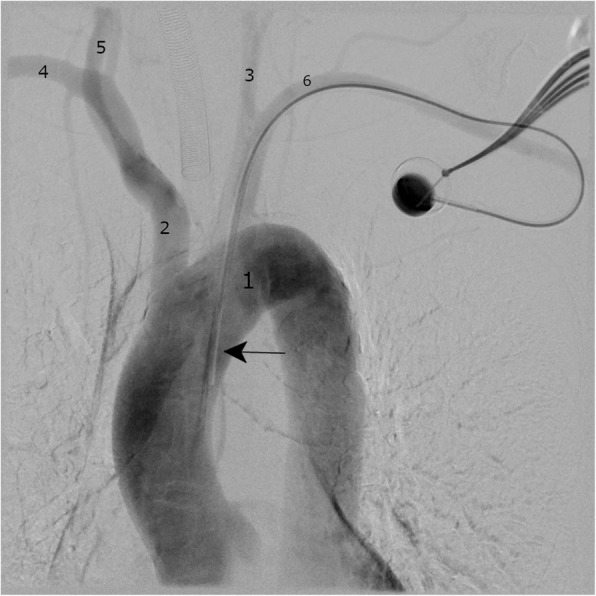

The patient was transferred immediately to a vascular surgery department. Conventional angiography showed an arterially placed catheter (Fig. 2) which was later removed during an open surgical exploration. Here, the catheter was found to be entering the left subclavian artery with an organized clot surrounding the catheter tip.

Fig. 2.

Intraoperative angiography of the aortic arch via port catheter system allows visualization of the misplaced port catheter and the supra-aortic arteries. Aortic arch (1), brachiocephalic trunk (2), left common carotid artery (3), right subclavian artery (4), right common carotid artery (5), left subclavian artery (6), tip of the catheter (arrow)